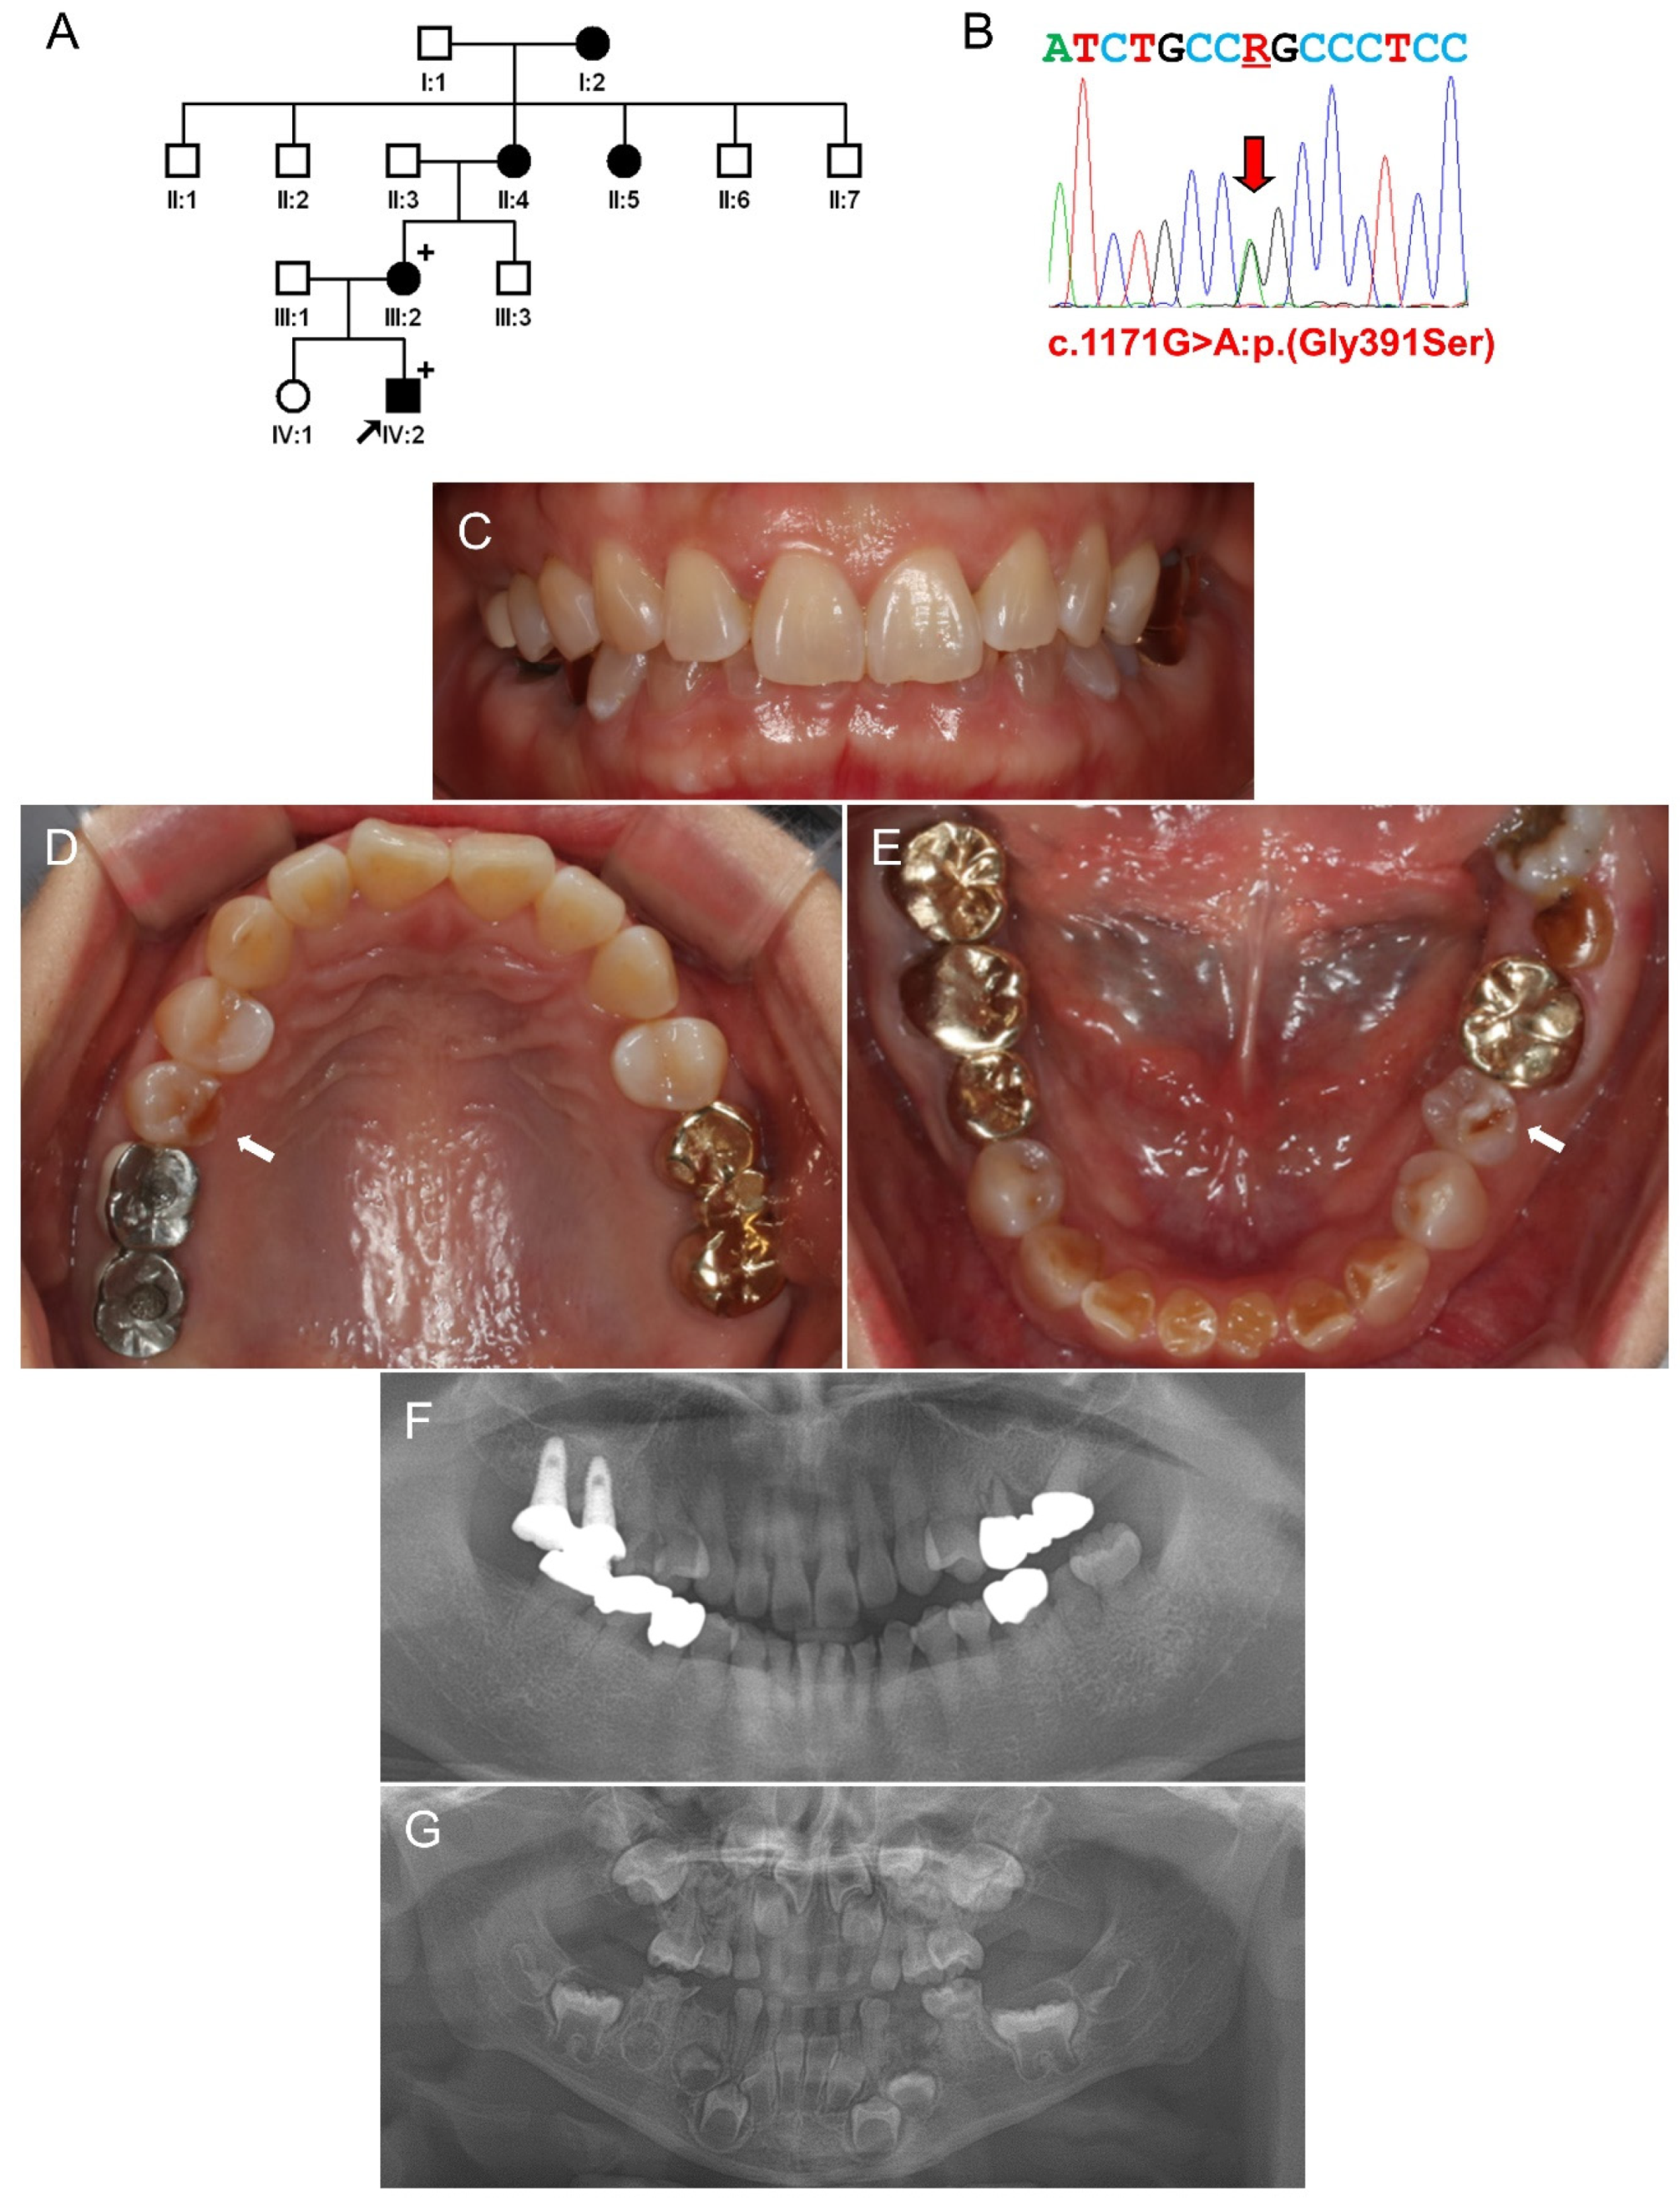

3.2. Family 2